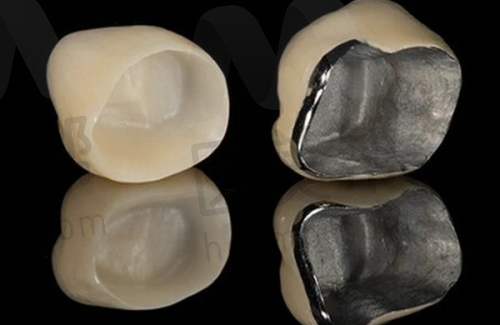

牙齿种植 | 使用方便,坚固稳定,不易松动,使用时间长,和真牙功能色泽接近 | 5000 - 260000元 |

补牙 | 防止疾病进一步恶化,消除不适,修复牙齿健康 | 800 - 11000元 |